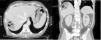

Varón de 66 años que ingresa por shock séptico abdominal y absceso hepático en TC (fig. 1). Las muestras sanguíneas mostraban un avanzado grado de hemólisis, con presencia de hematíes fantasma (flechas delgadas) y esferocitos (flechas gruesas) (fig. 2); y hemocultivos positivos para C. perfringens. El paciente presentó evolución desfavorable hacia disfunción multiorgánica con acidosis metabólica, anemización y trombocitopenia progresivas, sin respuesta al tratamiento, falleciendo a las 3h. La sepsis por C. perfringens tiene un pronóstico infausto si no se detecta de manera precoz. Ante un paciente séptico con datos de hemólisis masiva hay que tener presente esta entidad, solicitar hemocultivos y tinción gram de la extensión sanguínea, e iniciar antibioterapia empírica precoz con penicilina y clindamicina, además de desbridamiento local.